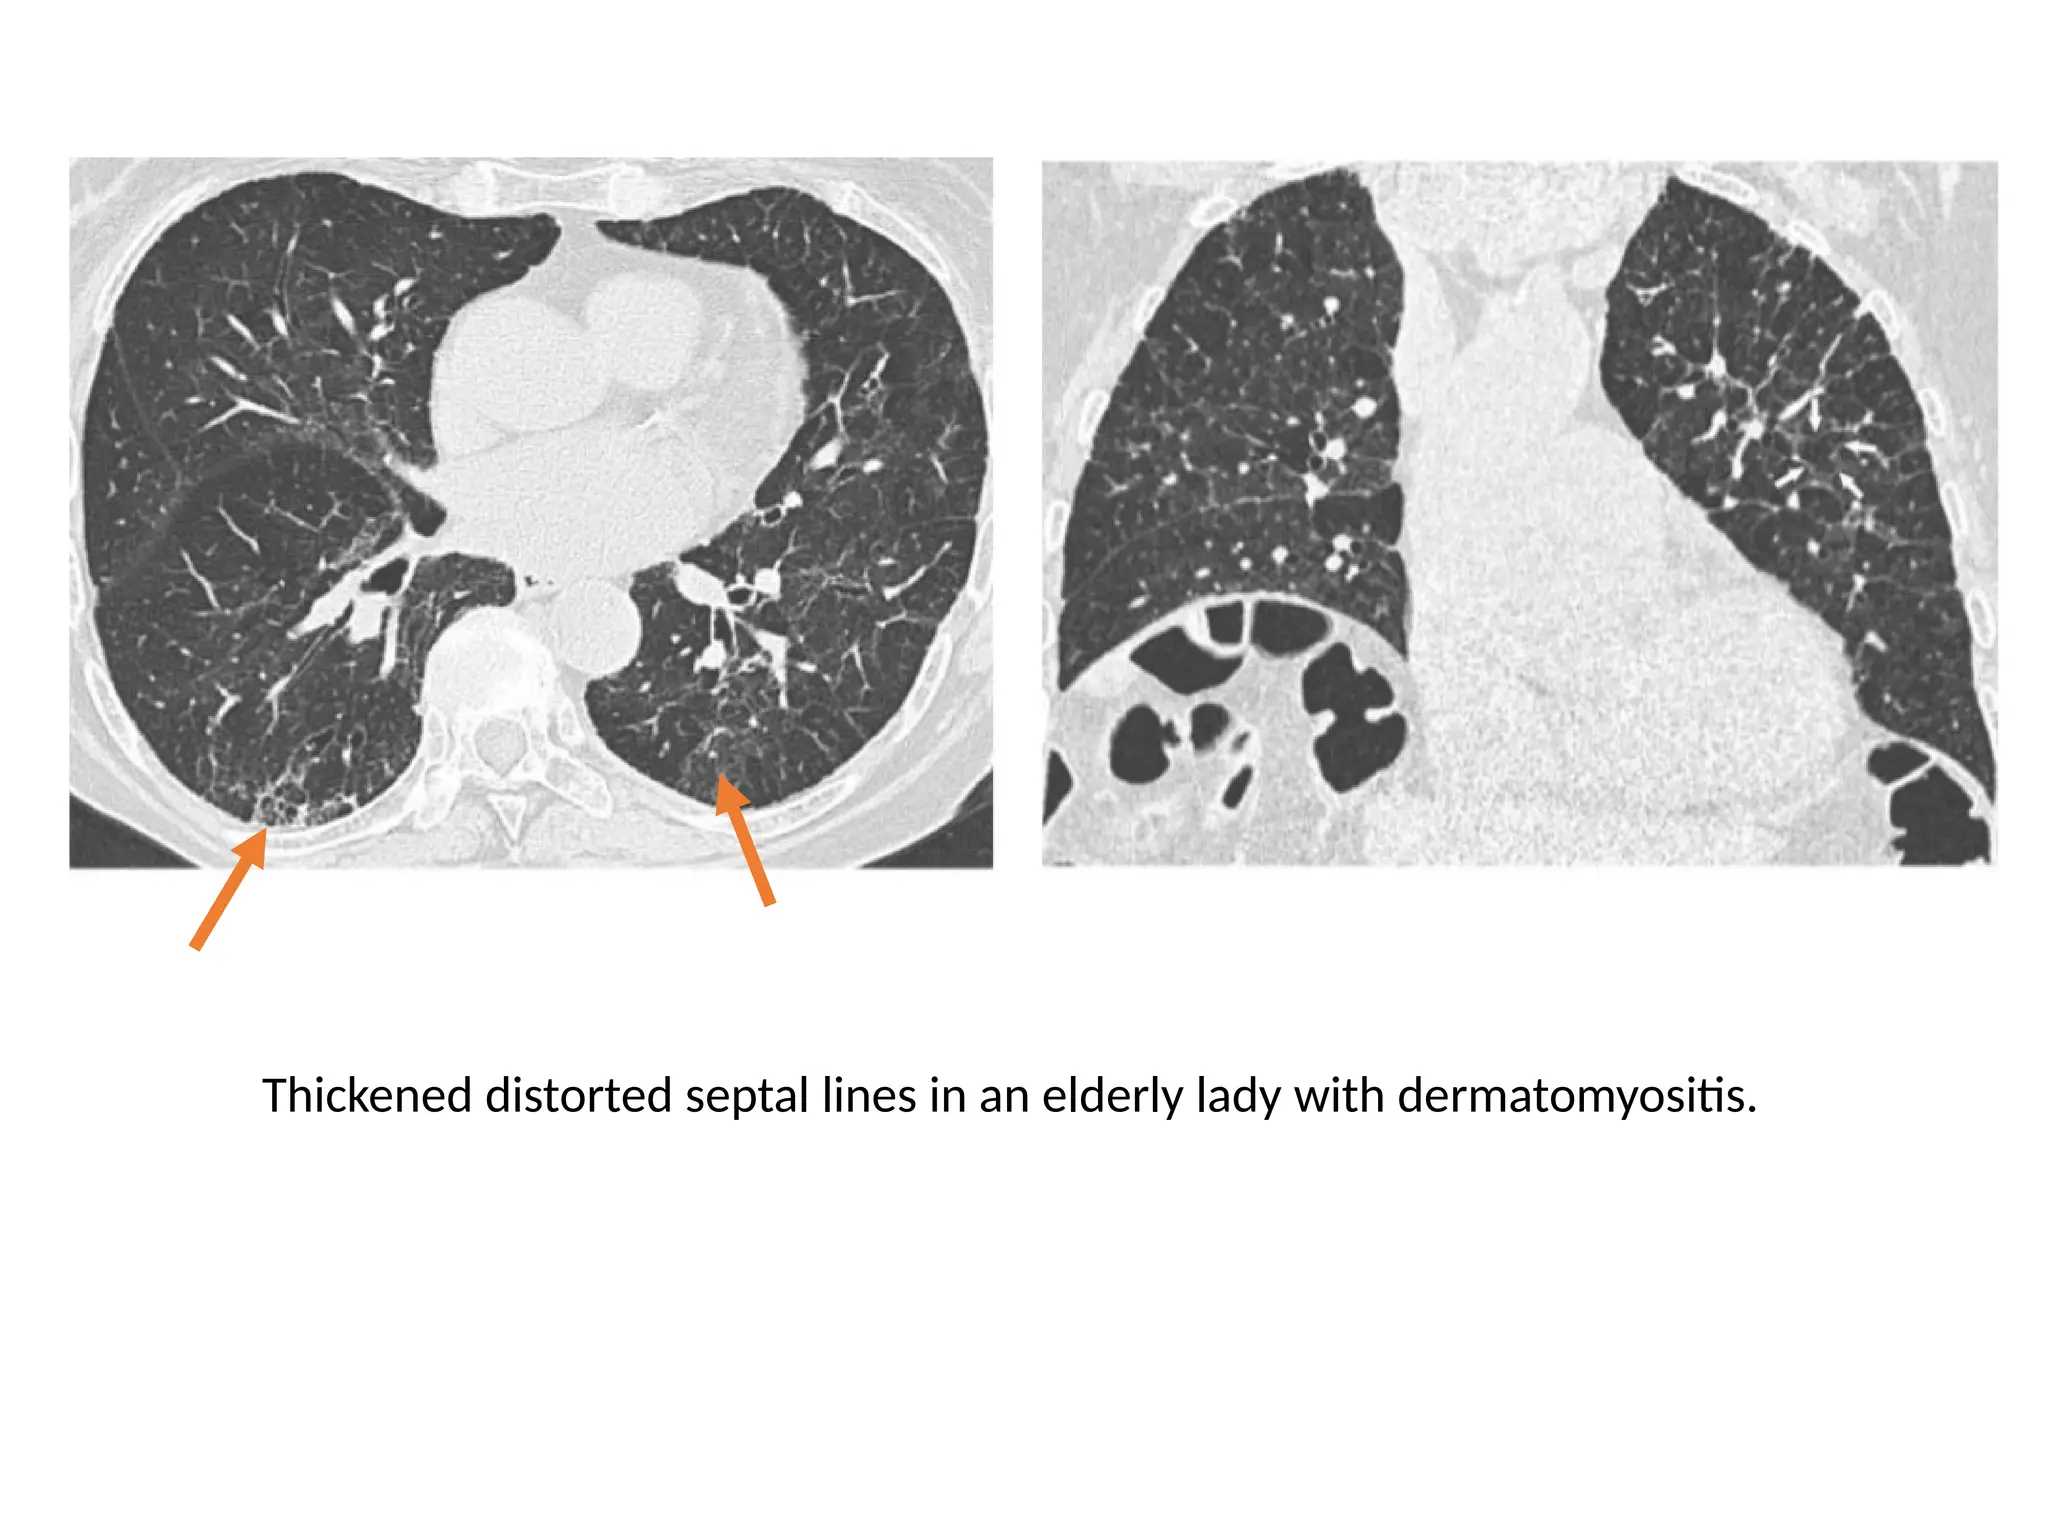

Thickened distorted septal lines in an elderly lady with dermatomyositis.

Thickened distorted septallines in an elderly lady with dermatomyositis.